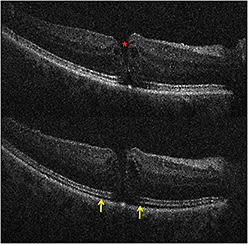

For ERM cases, residual membranes could be identified, and alterations to retinal architecture were also noted (Figure 3, page 28).1,4 Following membrane peeling, changes in the distance between the photoreceptor layers and the retinal pigment epithelium were qualitatively visualized, similar to previous descriptions.1,4,9 These included subtle changes in the hyporeflective band between the photoreceptor layers and the RPE, as well as more significant changes in full-thickness retina.1,9

Figure 3. Intraoperative OCT and ERM. (Top) Preincision intraoperative OCT B-scan revealing prominent epiretinal membrane (orange arrow). (Bottom) Postpeel intraoperative OCT B-scan revealing expansion of the subretinal hyporeflectivity band between the photoreceptor layers and the retinal pigment epithelium (yellow arrows). A residual membrane is also identified (red arrow).